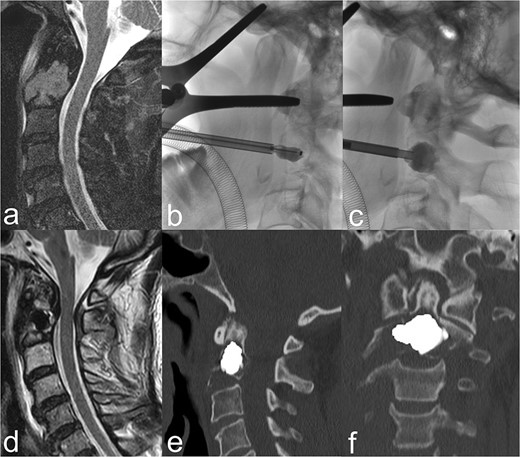

As a matter of routine, perioperative prophylactic single-shot antibiotic treatment was given with 2 g cefazolin (Cefazolin HEXAL® 2 g). The intervention was performed under intubation anaesthesia. The patient was then placed in the C-arm in the supine position with slight hyperextension of the cervical spine. The oropharynx was held open using a spreader. After the usual preparation and determination of the access plane, a Kirschner wire was first advanced transorally into the central tumour lesion of vertebral body C2. A 19-G hollow needle was then inserted via the wire. A 15 mm balloon catheter (Kyphon Xpander™ II system™) was introduced through this and inflated and deflated several times, partially overlapping, under fluoroscopy. The cavity prepared in this way was then successively filled with 2.6 ml of viscous PMMA cement (Kyphon VuE™ bone cement) using a low-pressure method, also under fluoroscopy (Fig. 1a–c).

(a) The sagittal heavily T2-weighted fat-suppressed MRI imaging shows myeloma-related osseous destruction/pathological fracture of the corpus vertebrae axis. (b) BKP via a transoral approach. (c) After removal of the balloon catheter, the cavity created is filled with PMMA cement. (d) Centrally located cement plug in the sagittal T2-weighted MRI slice. (e) and (f) The sagittal and coronal reformed CT slices show a cement plug located centrally in the lesion. Cement leakage can be ruled out.

BKP was technically fully feasible. The control CT showed a central cement distribution in the tumour lesion, whilst cement leakage could be excluded (Fig. 1d–f). A significant, rapid and sustained pain reduction developed from 9 score points on the VAS pre-intervention to 2 points on postoperative day 2 and complete freedom from pain under provoked movement after 6 months (Fig. 2). The patient was able to be quickly remobilised after the intervention and be passed on for the further planned therapeutic measures. Patient satisfaction with the procedure was high, whilst quality of life improved significantly subjectively and objectively. The patient would not hesitate to have the intervention performed again.

Successful interventional treatment of osseous destruction of vertebral body C2, via a transoral approach, has only been reported by individual working groups to date. The first cement augmentations for the treatment of a symptomatic angioma [27], an aneurysmal bone cyst [28], a metastasis from a thyroid carcinoma [29], and a multiple myeloma [30] were performed without relevant complications using the vertebroplasty technique, whereby a marked reduction in pain was achieved clinically. Monterumici et al. [31] were the first to perform transoral kyphoplasty in vertebral body C2 in three patients with osteolysis, one of whom was a 69-year-old woman with MM, with no complications and marked clinical improvement in terms of sustained pain reduction and fracture stabilization. BKP is an osteoplastic procedure in which a preformed cavity is created in the osseous lesion by inflation of a balloon for cement insertion, whilst the circumference is compressed, thus minimizing cement leakage [21, 22]. CT diagnostic imaging also ruled out leakage in our patient, with good central cement filling (Fig. 1e and f). In this respect, the risk of cement leakage would appear to be more likely with the vertebroplasty procedure [32].